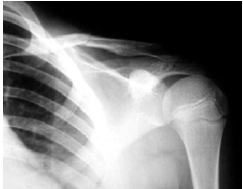

48 13 歲男童打棒球時撲壘受傷,就診時左肩痛,左臂不能抬舉,其 X 光片顯示如圖。則下列有關此傷 害之敘述,何者最正確?

①一般以外中內三分法來描述骨折 ②外觀上為斜形骨折 ③癒合不良為 常見之後遺症 ④一般分為外展形與內收形兩類 ⑤鈣化性肌炎為常見之後遺症 (A)①②③ (B)①②④ (C)②④⑤ (D)③④⑤